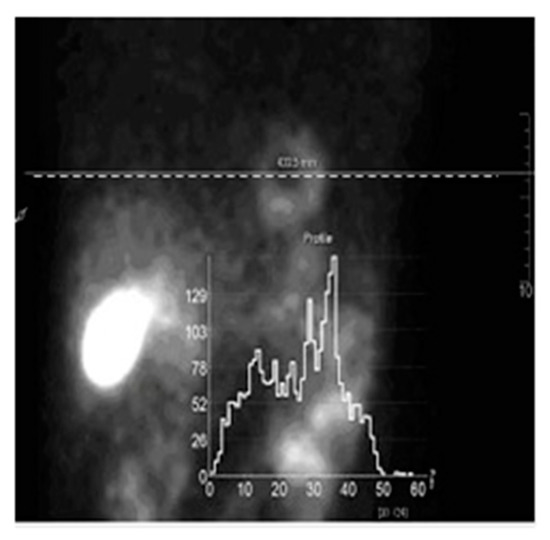

- OSEM—the standard non-regularized algorithm (9) applied on the most SPECT and PET systems;

- MAP-GIBBS—the Bayesian algorithm Maximum a Posteriori (MAP) with prior model based on the Gibbs distribution (14), global regularization;

- MAP-ENT—the MAP algorithm with prior model based on the entropy functional (34), global regularization; and,

- MAP-ENT-LOC—the MAP algorithm with prior model based on the entropy functional for open system (43), local regularization.

4. Results and Discussions